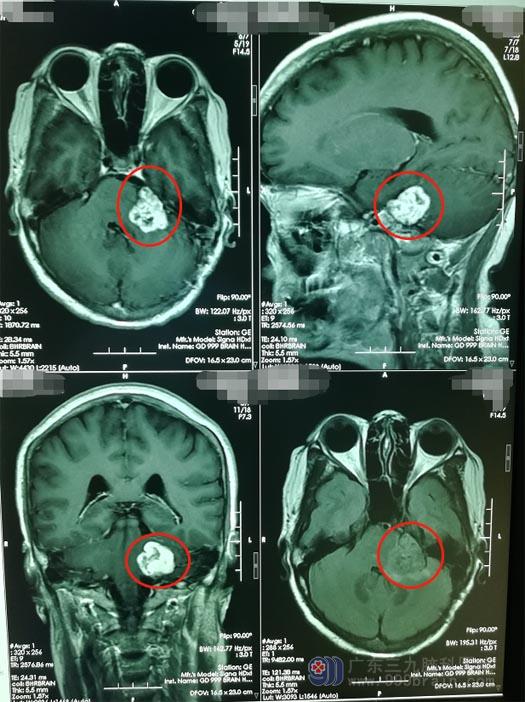

一个月前,徐阿姨觉得左边耳朵偶有耳鸣,伴有听力下降,这使她坐立不安,担心是肿瘤复发了,通过对多家医院进行比较后,徐阿姨在丈夫的陪同下来到了广东三九脑科医院神经外五科。进一步头部MR检查,结果显示 “左侧桥小脑角占位性病变”,考虑为听神经鞘瘤。徐阿姨最担心的事情还是发生了。

医院副院长、神经外五科主任鲁明带领治疗团队慎重地术前讨论后,由鲁明主刀为徐阿姨行“左侧桥小脑角占位切除术”,术中见肿瘤位于左侧桥小脑角区,血供丰富,肿瘤与面神经粘连,术中采用电刺激辨认面神经,保护了面、听神经功能,显微镜下分块将肿瘤全部切除,术程顺利。